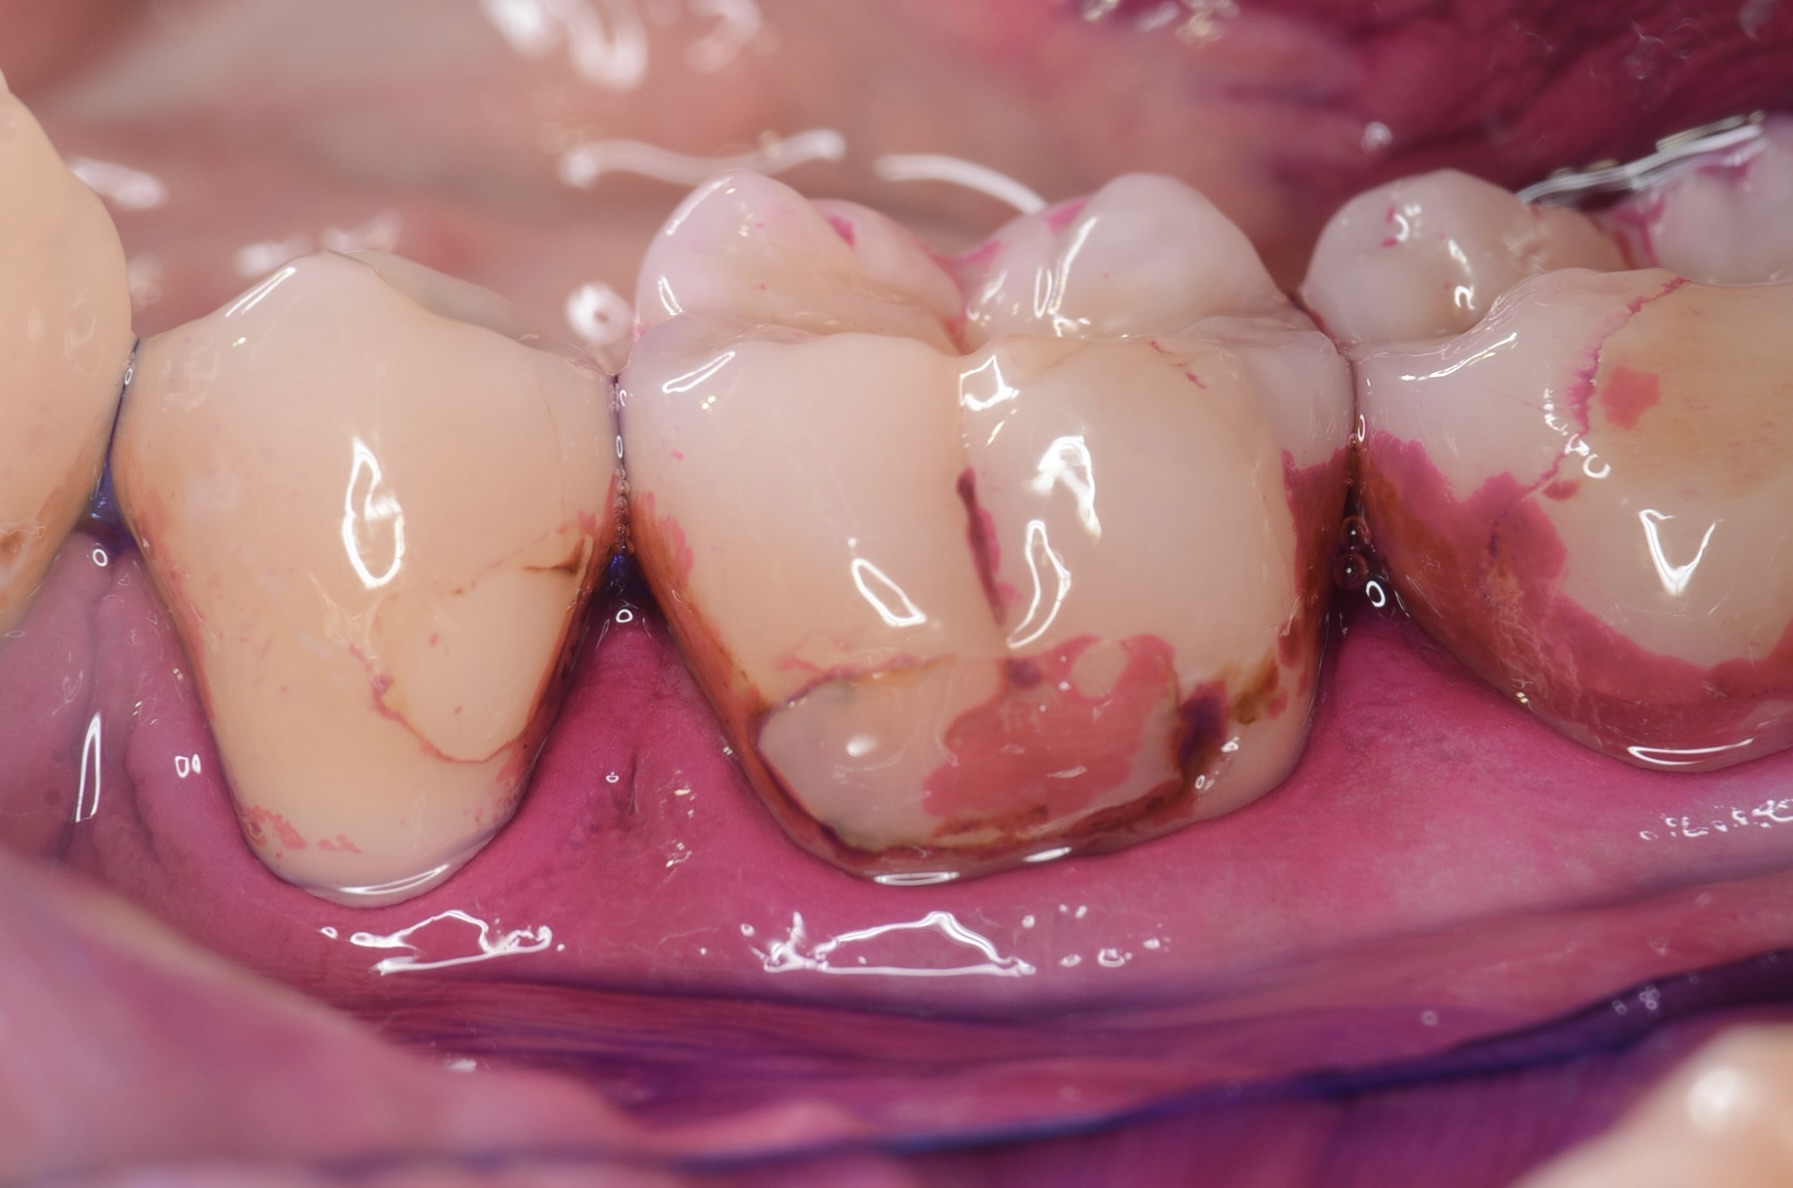

歯垢染め出し

歯垢は接着操作を妨げます。治療前には、必ず歯垢染め出し液により歯垢を見える化し、その後ジェットパウダークリーニングにより徹底的に除去します。保険診療ではここまでする事はほとんどありません。 -